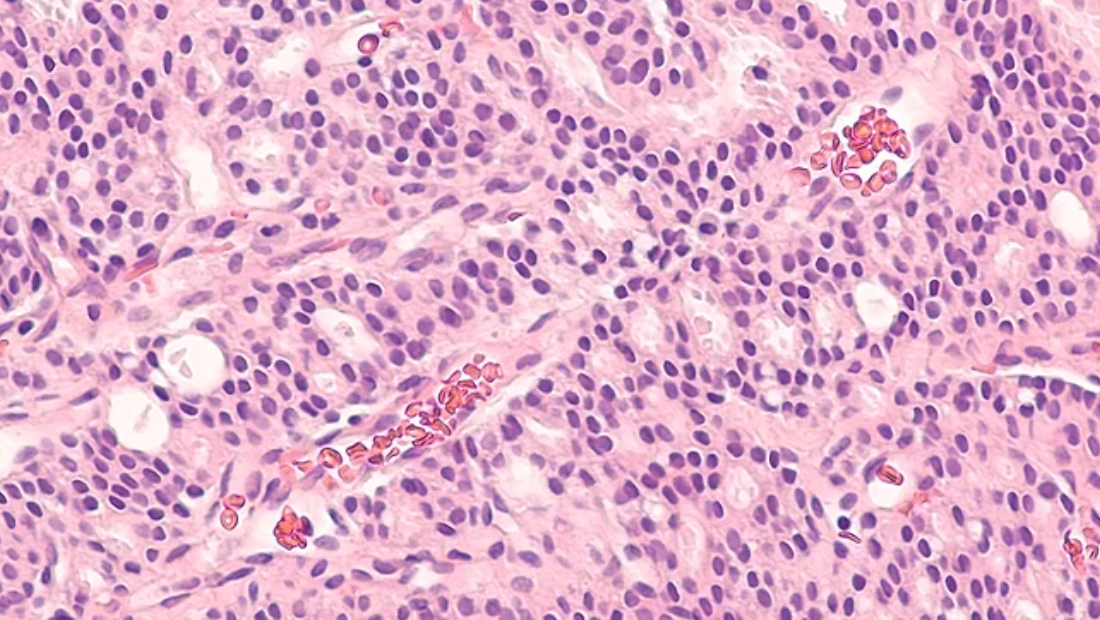

RIPTACs™ have the potential to offer stronger, more targeted cancer treatments by activating a killing signal only within tumor cells, thereby reducing side effects and improving patients’ quality of life compared to traditional therapies. In 2024, Canaan Executive in Residence, Chris Schade, took charge as President and CEO as the company transitioned to a clinical-stage company.

This November, Halda’s Phase 1 clinical data in patients with advanced metastatic prostate cancer were presented at a major medical conference. Treatment with Halda’s medicine, HLD-0915, resulted in profound benefit for these patients, which was even more striking given that they had failed all other available options. As one employee noted, many patients will enjoy the year-end holidays in much better spirits and with newfound hope thanks to Halda and HLD-0915.